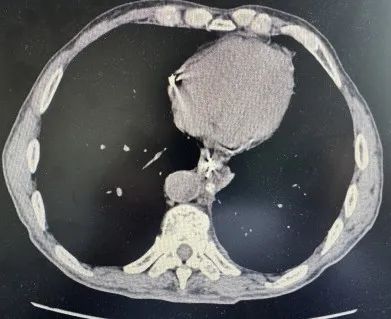

「我们充分打开患者的纵隔胸膜,先后用双氧水、生理盐水反复冲洗胸腔,直至将纵隔内的胃液、胃内容物、坏死物质和脓性分泌物清除后,分层缝合食管破裂口,确保吻合口牢固......」2 个多小时后,手术顺利结束,刘大爷安返病房,恢复良好。手术后第一天即可下地活动,复查床旁胸片可见胸腔内无明显积液,炎症中毒症状也逐渐缓解,行上消化道造影评估吻合口愈合良好后出院。最近刘大爷再次来医院复查,已经可以正常吃饭了。发生在刘大爷身上的自发性食管破裂是较为少见且异常凶险的病症,而主要原因可能就是刘大爷多年的便秘导致腹内压逐渐升高,最终导致胃内压持续升高而导致撕裂了食管壁。

(刘大爷最近复查的上消化道造影,可见吻合口愈合及胃排空良好,复查胸部 CT 可见纵隔窗无明显积液及积气,恢复良好)